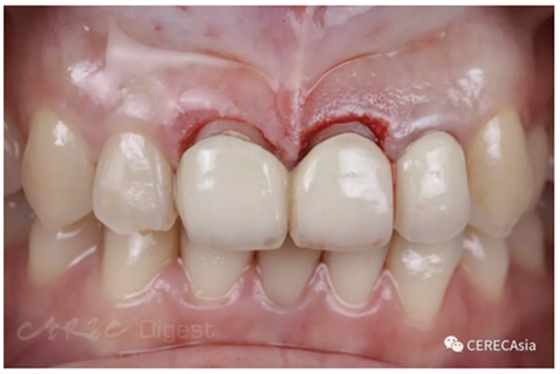

透過微笑分析與討論后,Sofia 同意進(jìn)行牙冠延長手術(shù)。

以水雷射輔助牙冠延長手術(shù),重新建立牙齦高低高 (high-low-high) 的型態(tài),并改善露齦笑(gummy smile)。

圖二、水雷射牙冠延長術(shù)后照。